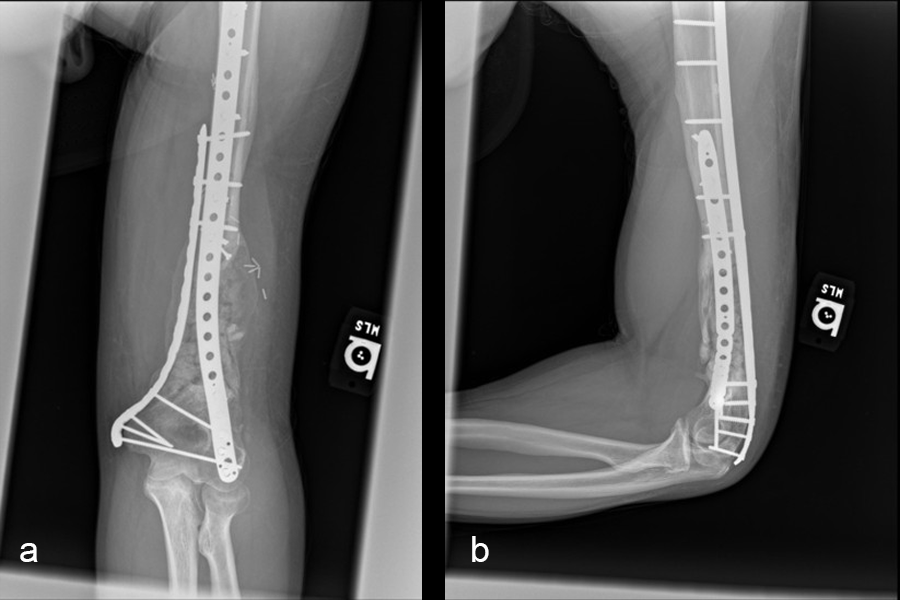

The second stage of surgery took place in October 2022. The cage was inserted (Figs 20-22) and filled with ~20cc autograft obtained by RIA of the femur, 30cc allograft and 3cc BMAC.